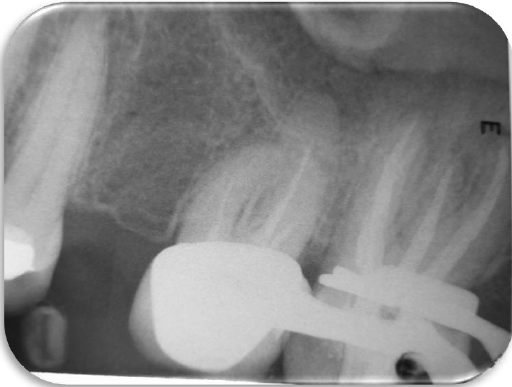

Se realizó protocolo final de irrigación con Hipoclorito de Sodio al 5.25 % activándolo con el ultrasonido (NSK Varios 370, Japan) y la punta #30 del Endo Kit E12 (NSK, Japan). La obturación se realizó utilizando cemento sellador Sealepex (SybronEndo Kavo Kerr, USA) con técnica lateral modificada con ultrasonido (NSK Varios 370, Japan) y la punta #30 del Endo Kit E12 (NSK, Japón) (Figuras 4 y 5).